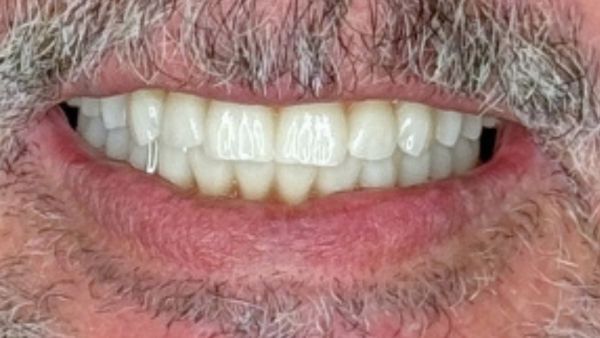

Implantes y Dientes Fijos en 24 horas